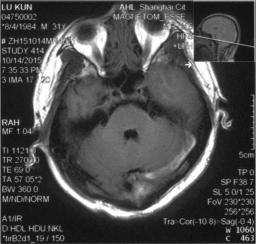

脑MRI:左侧横窦条索状高信号,左颞叶脑出血,见图3&6、7、8

图3

图6

图7

图8